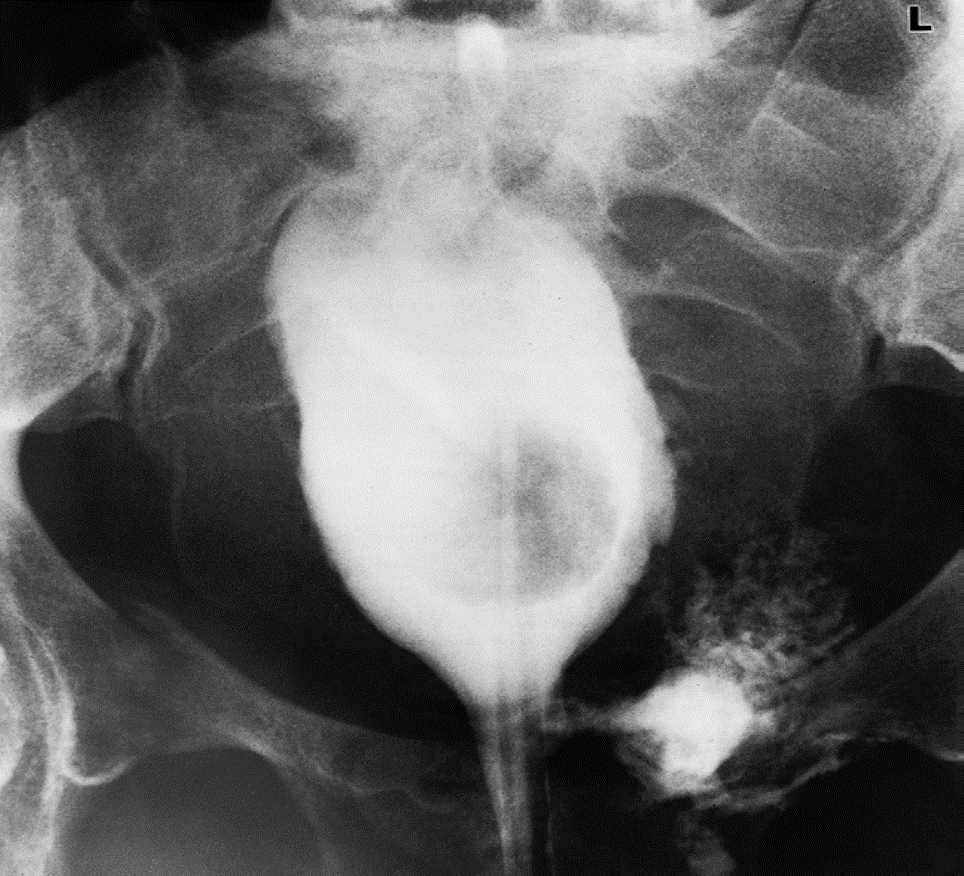

Rupture of the base of the bladder.

Cystogram showing extravasation of contrast into the extraperitoneal space on the left, and deformity of the bladder due to surrounding haematoma and urine. There is a fracture of the right pubic bone.